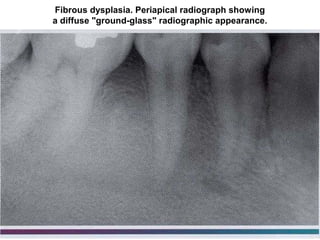

Fibrous dysplasia. Periapical radiograph showing

a diffuse "ground-glass" radiographic appearance.